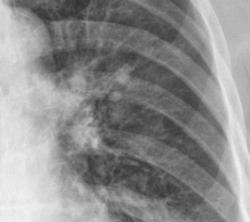

Мы, конечно можем предполагать, что это усиление или обогащение легочного рисунка, высказывать предположение, что это "пневмонические изменения" или перисциссурит и т.д. и т.п., но без боковой проекции - это увы только предположения или рассуждения. Нужна боковая - боковые.

Конечно соглашусь с Валентином Львовичем. Без боковых можно только предполагать. Но скорее всего пневмония в S6 и S10 слева. Десятый сегмент слева, как раз за тенью сердца.